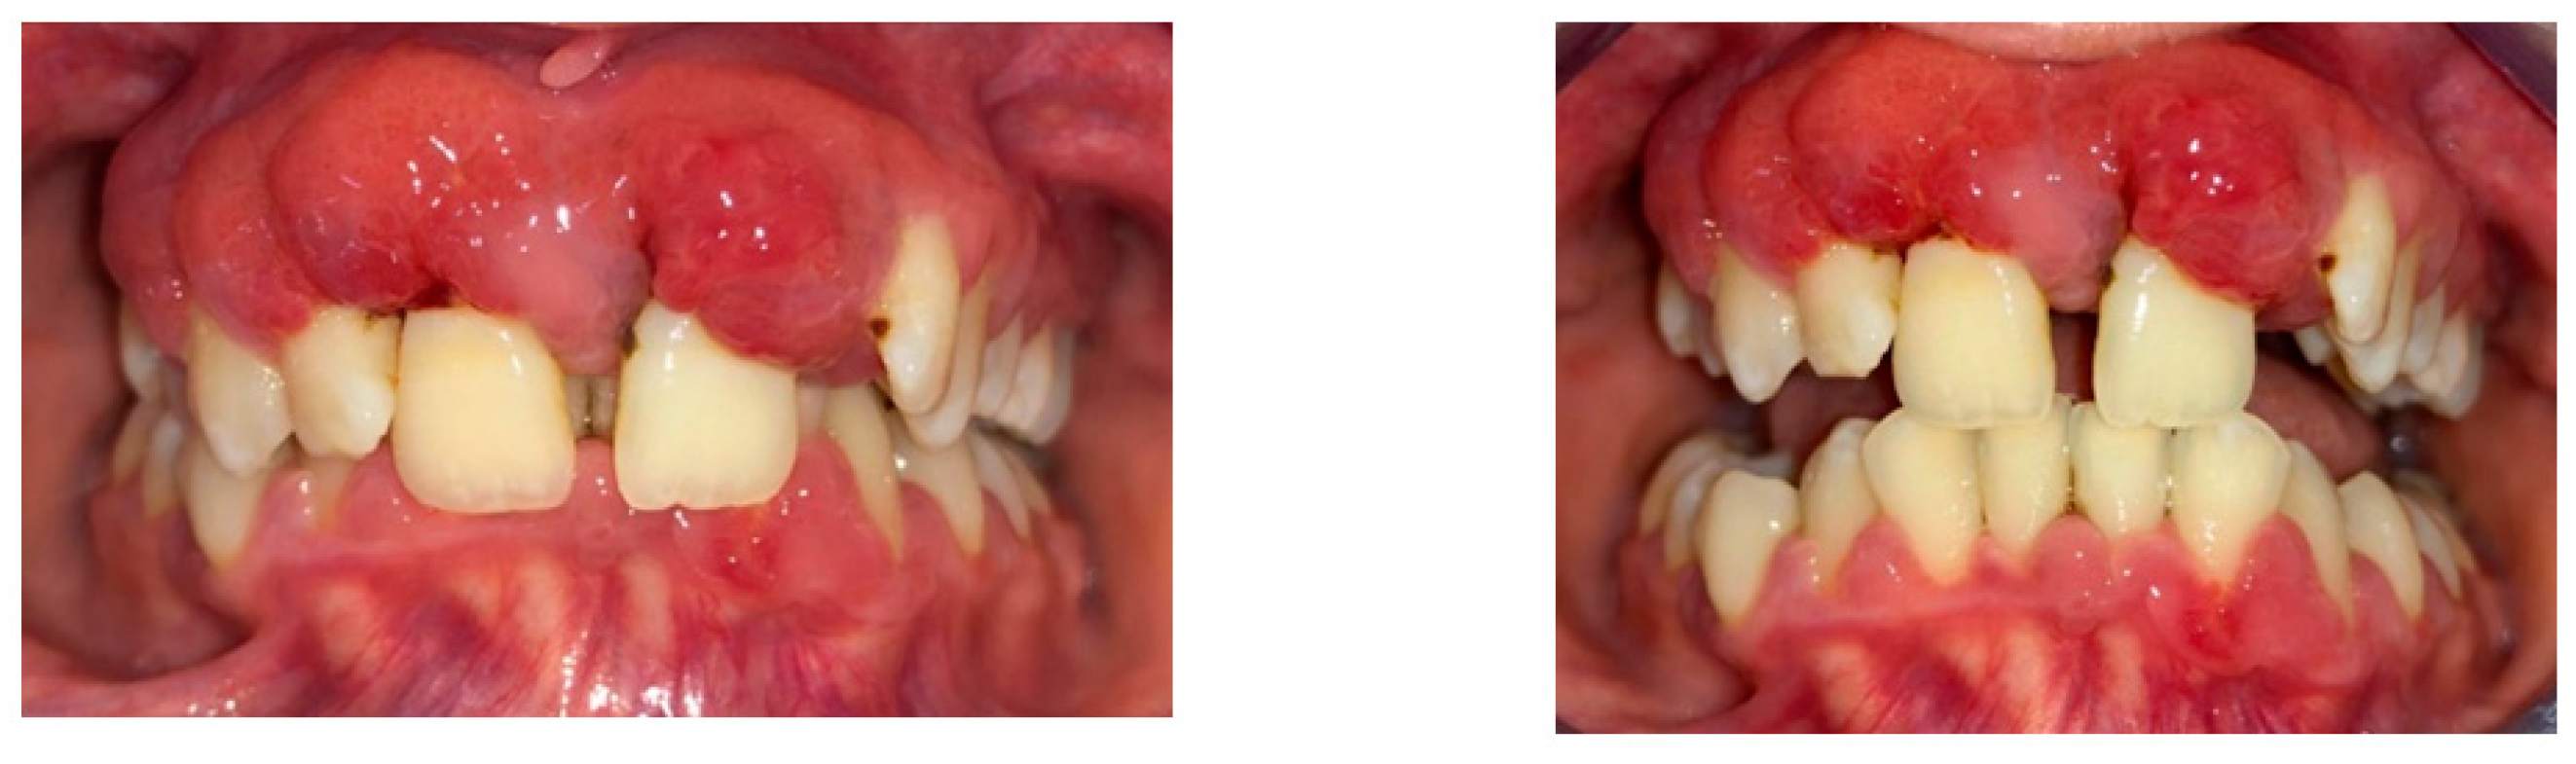

A 15-year-old female teenager was referred by a general practitioner to the Department of Periodontology, Faculty of Dental Medicine, University of Medicine and Pharmacy Carol Davila, Bucharest, Romania. There were no other diseases, such as diabetes or other hematological disease, no smoking, and no medications being taken by the patient. She had an accident (falling down the stairs) when she was 7 years old but did not experience any general or dental trauma (without notable objective or subjective clinical signs) as a result. Consequently, she did not visit a dentist for any treatment. The reasons for the first visit were teeth mobility, which appeared 2 years behind, poor aesthetic aspect of gingiva, and poor masticatory performance. The following clinical parameters were assessed at baseline: bleeding upon probing (BOP), plaque index score (O’Leary et al.) [12] and probing depth (PD). All measurements were performed by the same examiner using a periodontal probe (North Carolina 15 mm probe) on six sites for each tooth. The initial examination revealed deep probing pocket depth, severe gingival overgrowth, bleeding upon probing, and gum recession. Gingival inflammation was observed. Periodontal abscesses were registered to both maxillary central incisors (Figure 1). Suppuration and tooth mobility were registered to both maxillary central and lateral incisors. Gingival overgrowth was registered mainly on the maxillary anterior tooth side.

Figure 1.

Clinical aspects before periodontal treatment: (a) frontal aspect, (b) right lateral aspect, (c) left lateral aspect, (d) maxillary occlusal aspect, and (e) mandibular occlusal aspect.

The plaque index score registered and bleeding upon probing (BOP) were 100%. The initial probing depth (PD) was 10 mm at the left central incisors (mesial) and 8–9 mm at the other proximal sites of the both upper central incisors. The tooth mobility (Miller Classification) was Class 2 for both the maxillary central and lateral incisors (Figure 2).